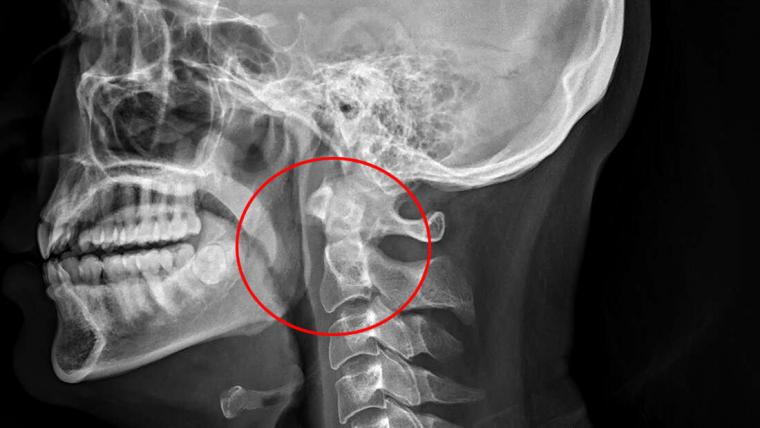

Οι γιατροί το αναγνωρίζουν αυτό με την ορολογία “σημάδι του Χάμαν”. Μπορεί να συμβεί όταν καθώς συστέλλεται και διαστέλλεται η καρδιά, χτυπάει πάνω σε ιστό γεμάτο με αέρα. Οι γιατροί διέταξαν επιτόπου να γίνει ακτινογραφία. Εκεί αποκαλύφθηκε το πρόβλημα:

Καθώς “κράτησε” το φτέρνισμα, ο 34χρονος είχε σπάσει το πίσω μέρος του λαιμού του!

Η ρήξη (η οποία προκαλείται συχνότερα από αμβλύ τραύμα στον λαιμό, έντονο έμετο και βαρύ βήχα) είχε προκαλέσει διαρροή αέρα στην οπισθοφαρυγγική περιοχή (δείτε το βέλος στην ακτινογραφία), προκαλώντας πόνο και απώλεια φωνής.